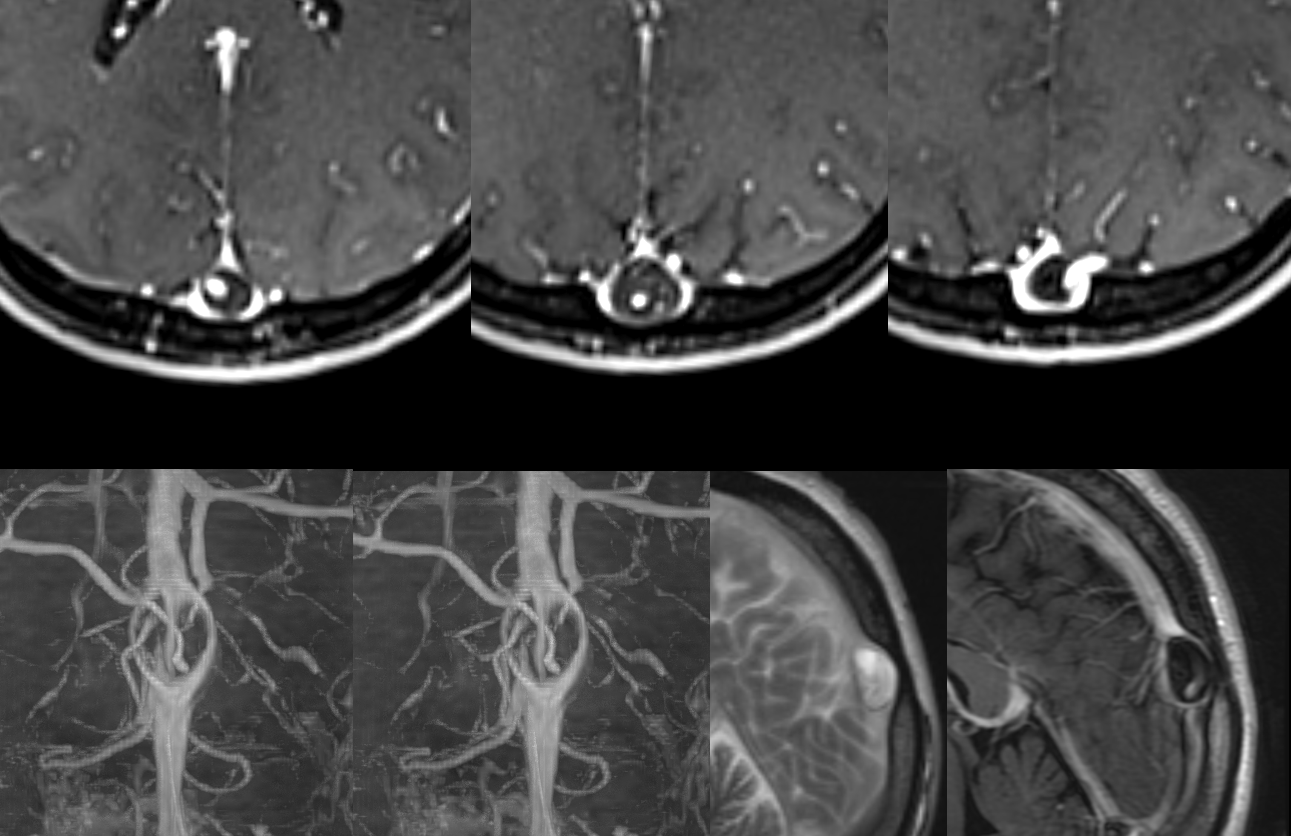

All of the above anatomic knowledge can become very useful in evaluation of venous thrombosis. Numerous collateral pathways develop in this setting attempting to compensate for the loss. The most dramatic cases usually involve the largest channel — the superior sagittal sinus. In this case, a man presented with what initially was thought to be vasculitis-related brain hemorrhage. Subsequent workup led to an angiogram, where sagittal sinus thrombosis with extensive trans-cerebral and trans-osseous emissary vein collateral channels was seen. In retrospect, these findings were present on the patient’s earlier contrast MRI. “Venovibe” or other contrast-enhanced MR venograms can very sensitive, particularly when interpreted with the appropriate index of suspicion. Noncontrast 2-D time of flight MRV I consider to be next to useless as a problem-solving technique. Any thin-slice postcontrast T1 study is vastly superior.